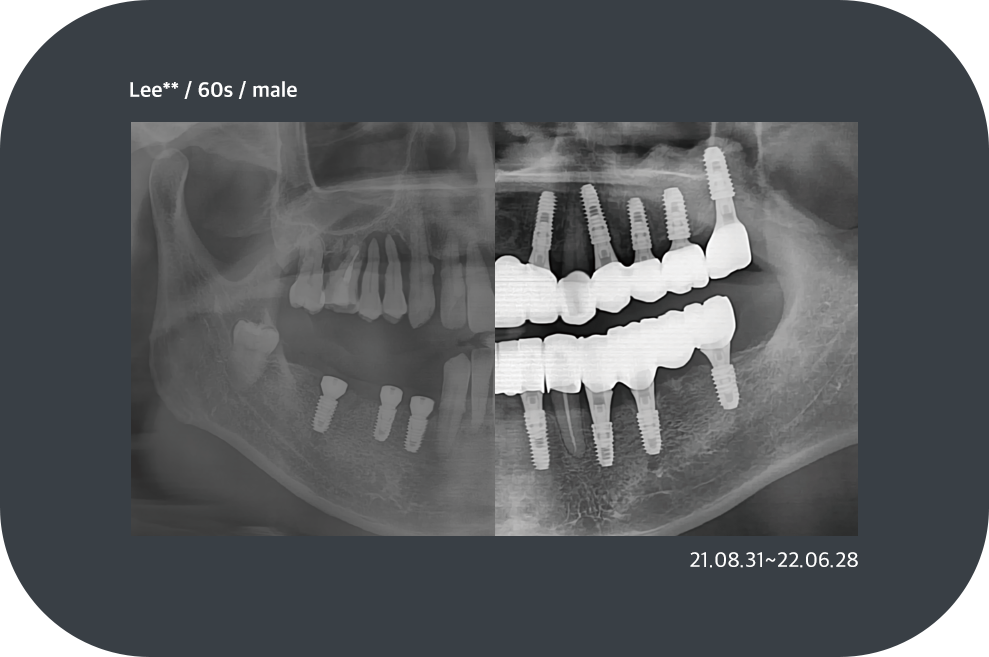

치료사례

임플란트 치료사례

implant_case01

implant_case02

implant_case03

implant_case04

*모든 증례 사진은 의료법 제23조, 제56조에 의거하여, 당사자의 동의하에 게시하였습니다.

*치료 사진은 모두 본원에서 치료한 환자분의 사진입니다.

*치료 사진은 모두 동일인의 사진이며, 동일조건에서 촬영하였습니다.

*개인의 차이에 따라 시술 및 수술 후 부작용이 발생할 수 있으며, 의료진과 충분한 상담을 받으시기 바랍니다.